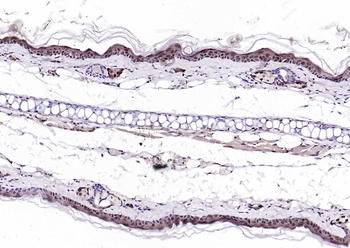

CDKN1A Antibody

Catalog Number: orb682382

| Description | CDKN1A Antibody |

| Target | CDKN1A |

200 μl, 50 μl, 100 μlCDKN1A/p21 Rabbit Polyclonal Antibody [orb11203]

FC, ICC, IF, IHC-Fr, IHC-P

Bovine, Canine, Gallus

Human, Mouse, Rat

Rabbit

Polyclonal

Unconjugated

50 μl, 100 μl, 200 μlPhospho-PAK6 (Ser560) Rabbit Polyclonal Antibody [orb6634]